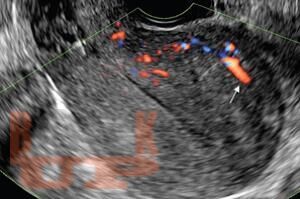

Особенности диагностики различных форм эндометриоза

В учебном пособии на современном уровне освещены вопросы диагностики эндометриоза различной локализации. Предназначено для врачей акушеров-гинекологов с целью формирования научно-обоснованного подхода в диагностике эндометриоза и его локализаций с целью обнаружения заболевания на ранних стадиях и сохранения репродуктивного здоровья женщины.